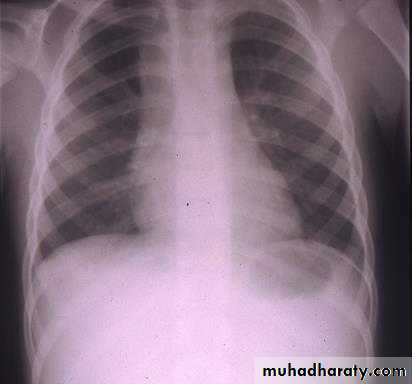

Asymptomatic mediastinal mass discovered by CXR

mediastinal adenopathy at presentation occurs in 60% of patients

Thoracic imaging

• Chest X-ray, CT scan of chest (ant/middle mediastinum) for best visualization of lung parenchyma, pleura